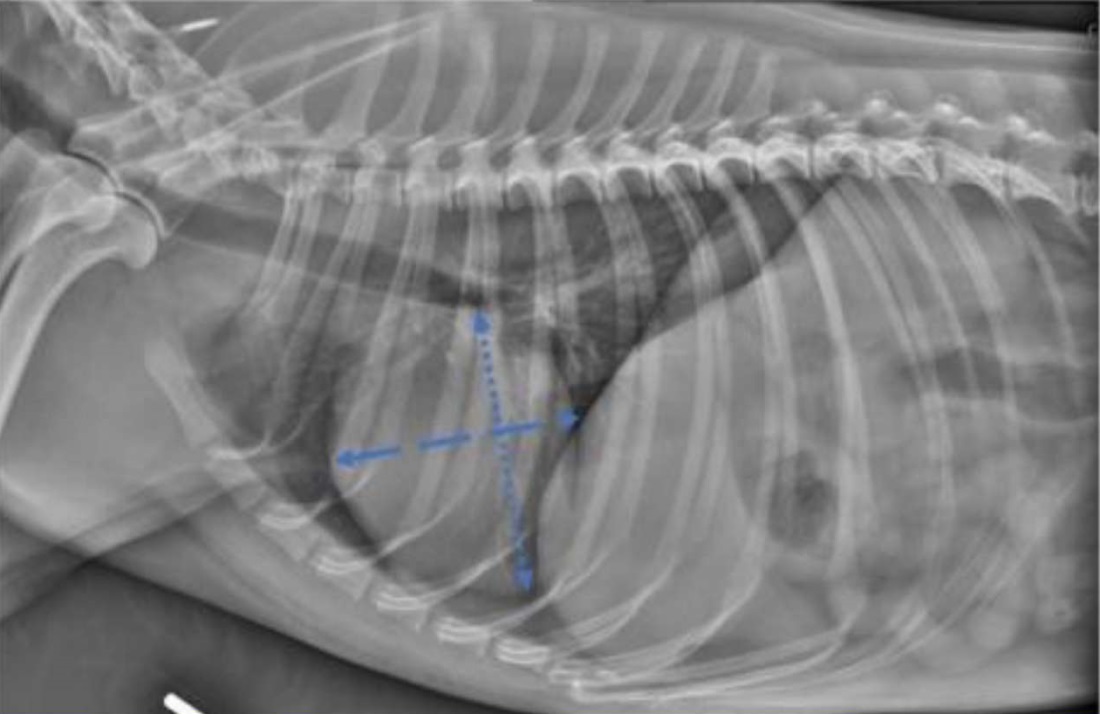

Currently, in veterinary medicine, one of the most reliable approaches for assessing the size of the cardiac silhouette on X-rays is Vertebral Heart Scale (VHS) measurement — calculating the ratio of the sum of the lengths of the short and long axes of the heart silhouette to the length of the thoracic vertebral bodies. Fig. 1 shows a lateral radiograph of a canine thorax, which presents the principle of measuring the cardiac axes [1].

Fig. 1. Principle of vertebral heart scale measurement [1]

The long axis of the heart is measured from the ventral border of the left main bronchus to the most remote ventral point of the apex of the heart. The short axis is measured along a line perpendicular to the long axis, at the level of the caudal vena cava. The sum of the lengths of the two axes is compared to the length of the vertebrae, starting from the cranial edge of T4 (the fourth thoracic vertebra) [2]. This technique has been proposed as one of the methods for assessing cardiomegaly in dogs and cats.